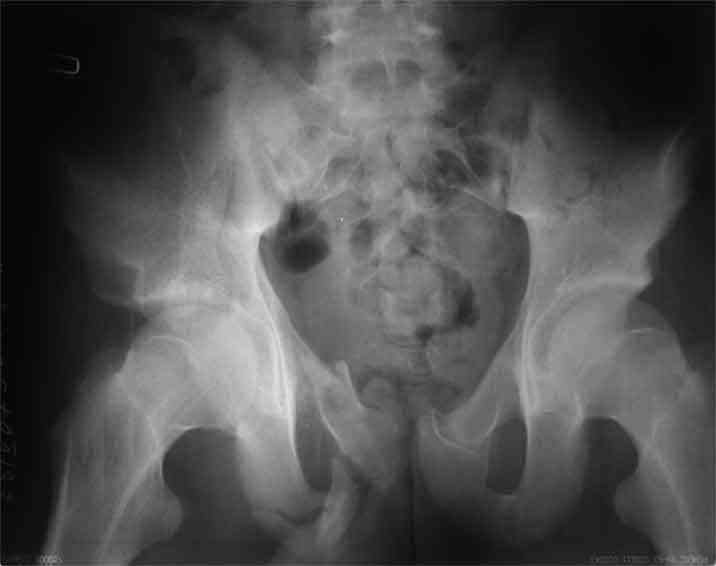

А чего там собственно таинственного? Билатеральное ротационно-нестабильное повреждение таза, перелом крестца в I зоне (по Denis)справа,частичное повреждение левого КПС, оскольчатые переломы лонной, седалищной костей справа (В3.2). Повреждение достаточно стабильное + молодой возраст+ сроки - оперативного лечения не требует.

Не смог разглядеть на представленных картинках частичное повреждение левого КП, повреждение Денис1-2 справа? 3Д реконструкции в инлет и боковой проекциях убедительно не демонстрируют типа повреждения задних отделов тазового кольца(справа боковая масса скомпремирована), Наверное, у тебя есть возможность оценить тип перелома крестца по прямой проекции 3Д.

по Pennal et al.- латеральное компрессионное повреждение тип В(ротационно-нестабильное (внутренняя ротация), вертикально стабильное)

по Tile classif. тип В2-1 - частично стабильное повреждение с неполным разрывом задней дуги.

По вертлуге- смог разглядеть только изолированный перелом передней колонны.

Насколько я понял из твоего письма, обращенного к анонимному vit, ты не видишь показаний к реконструкции перелома. Я бы взялся за реконструкцию(илео-ингвинальный доступ), хоть прошел и месяц после травмы: боковая 3Д показывает смещение нагрузочной зоны впадины, что однозначно будет способствовать разрушению хряща головки и впадины( особенно у 16 летнего пациента с ожидаемым высоким уровнем активности) + изменение геометрии впадины за счет неустраненного смещения фрагментов колонны (КТ, 3Д данные).

На мой взгляд, без реконструкции этот сустав обречен (концепция вторичной конгруэтности в данных условиях работать не будет), реконструкция дает шанс на восстановление функции сустава.

В данном случае 3D и корональные срезы КТ менее информативны, чем поперечные. Согласен с левосторенним минимальным повреждением КПС, но не смог уловить перелом крестца.

По представленным материалам, мне кажется, перелом был передней колонны ацетабулум с минимальным вовлечением нагрузочной поверхности сустава, левосторенний повреждение КПС и лонных костей.

При свежем случае показана фиксация передней колонны к задней (снимки), компрессирующим винтом минимальным перкутанным методом по супраацетабулярной линии и в зависимости от состояния КПС.